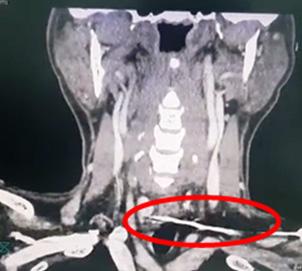

Turn static files into dynamic content formats.

Create a flipbook

Issuu converts static files into: digital portfolios, online yearbooks, online catalogs, digital photo albums and more. Sign up and create your flipbook.